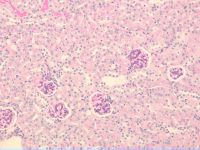

Normal appearing kidney in 26-wk-old FVB-+/? female [Consortial]

FVB.BKS(D)-+/?/ChuaJ

6654F34

Animal Age

26 week(s) post-natal (w)

Anatomical Site

Periodic acid Schiff (PAS)

200 X

normoglycemic FVB-+? control female; Body weight at 24 wk = 24.6g; plasma

glucose = 178 mg/dl; plasma insulin = 1.5 ng/ml; DEXA = 28.8% fat. ACR spot

urine at 21 wk = 43; ACR 24 hr urine collection at 25 wk = 43.

Microscopic Description

no visible lesions